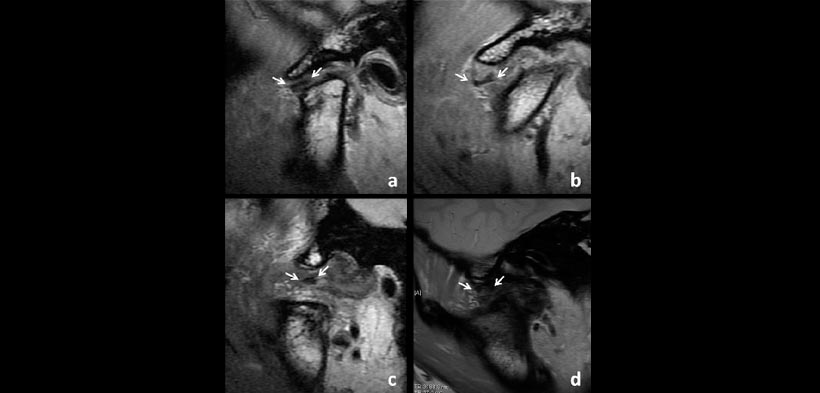

Fig. 4. La forma de disco lateral en la anquilosis de ATM Tipo. (A) Biplanar, (b) hemiconvexo, (c) biconvexa, (d) amorfo. Las flechas indican el disco.